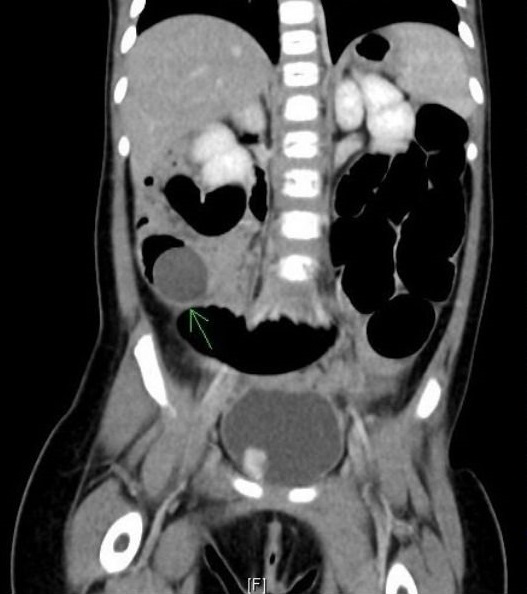

高雄长庚儿童胃肠科赖宛孜医生表示,X光片中男童小肠有阻塞及涨大情形,因此安排腹部电脑断层扫描,发现男童右下腹有圆形异物导致小肠阻塞,紧急连同小儿外科医生进行剖腹探查手术。

手术过程中,取出大小不一的异物,确认是完整的水晶宝宝,还有其他胀破的残渣。不过手术后持续观察,发现男童仍有胀痛、呕吐情形,再次安排X光片检查,发现男童腹部仍有尚未取出的的水晶宝宝,因此安排第二次开刀。